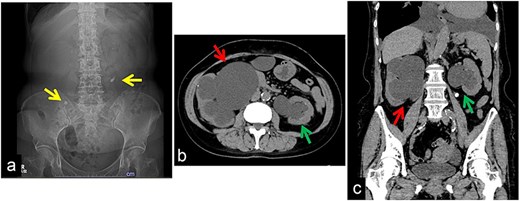

Transthoracic echocardiography showed severe left ventricular systolic dysfunction with a left ventricular ejection fraction (LVEF) of 24% by Simpson’s method (Fig. 2a). Kidney–ureter–bladder radiography and computed tomography performed to investigate systemic causes revealed severe bilateral hydronephrosis due to bilateral impacted ureteral stones (left: 17 × 7 mm; right: 10 × 8 mm; attenuation ~1350 HU) (Fig. 3). Retrograde ureteral stent placement was attempted on the same day but failed because contrast medium could not pass through the obstructed segments (Fig. 4). A left percutaneous nephrostomy (PCN) was therefore performed, followed by right PCN one week later. Concomitantly, guideline-directed heart failure therapy was initiated, including spironolactone (12.5 mg/day), empagliflozin (10 mg/day), sacubitril/valsartan (100 mg/day), and bisoprolol fumarate (1.25 mg/day).

Initial kidney, ureter, and bladder (KUB) and computed tomography (CT) findings. (a) KUB on admission showing a right ureteral stone in the pelvic region and a left ureteral stone in the upper ureter (U1). (b) Axial CT image demonstrating marked bilateral hydronephrosis. (c) Coronal CT image confirming severe bilateral hydronephrosis.